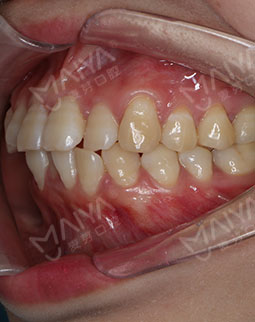

在主任的建议下拔了牙,根据我的牙齿情况,主任做了适合我的矫牙方案。选择了时代天使双膜矫治器,矫治器是透明的,可以自行摘戴,满足了我想矫正又怕丑的要求,让我在别人不知道的情况下,拥有整齐的牙齿,在矫正之前是可以在计算机上模拟显示整个矫治过程中牙齿的变化过程,可以很直观的看到,让我自己感觉心里很放心,经过一个月的等待,终于戴上了牙套,给主任和麦芽点赞!

2017-12-1不让自己留遗憾,我与歪牙要打持久战

经过朋友良心推荐,最终选择了麦芽口腔。在麦芽是张超主任给我检查的牙齿,然后跟着医助拍的片,这期间都有专人负责,张主任很专业的为我定制了方案,当天就取了牙模~